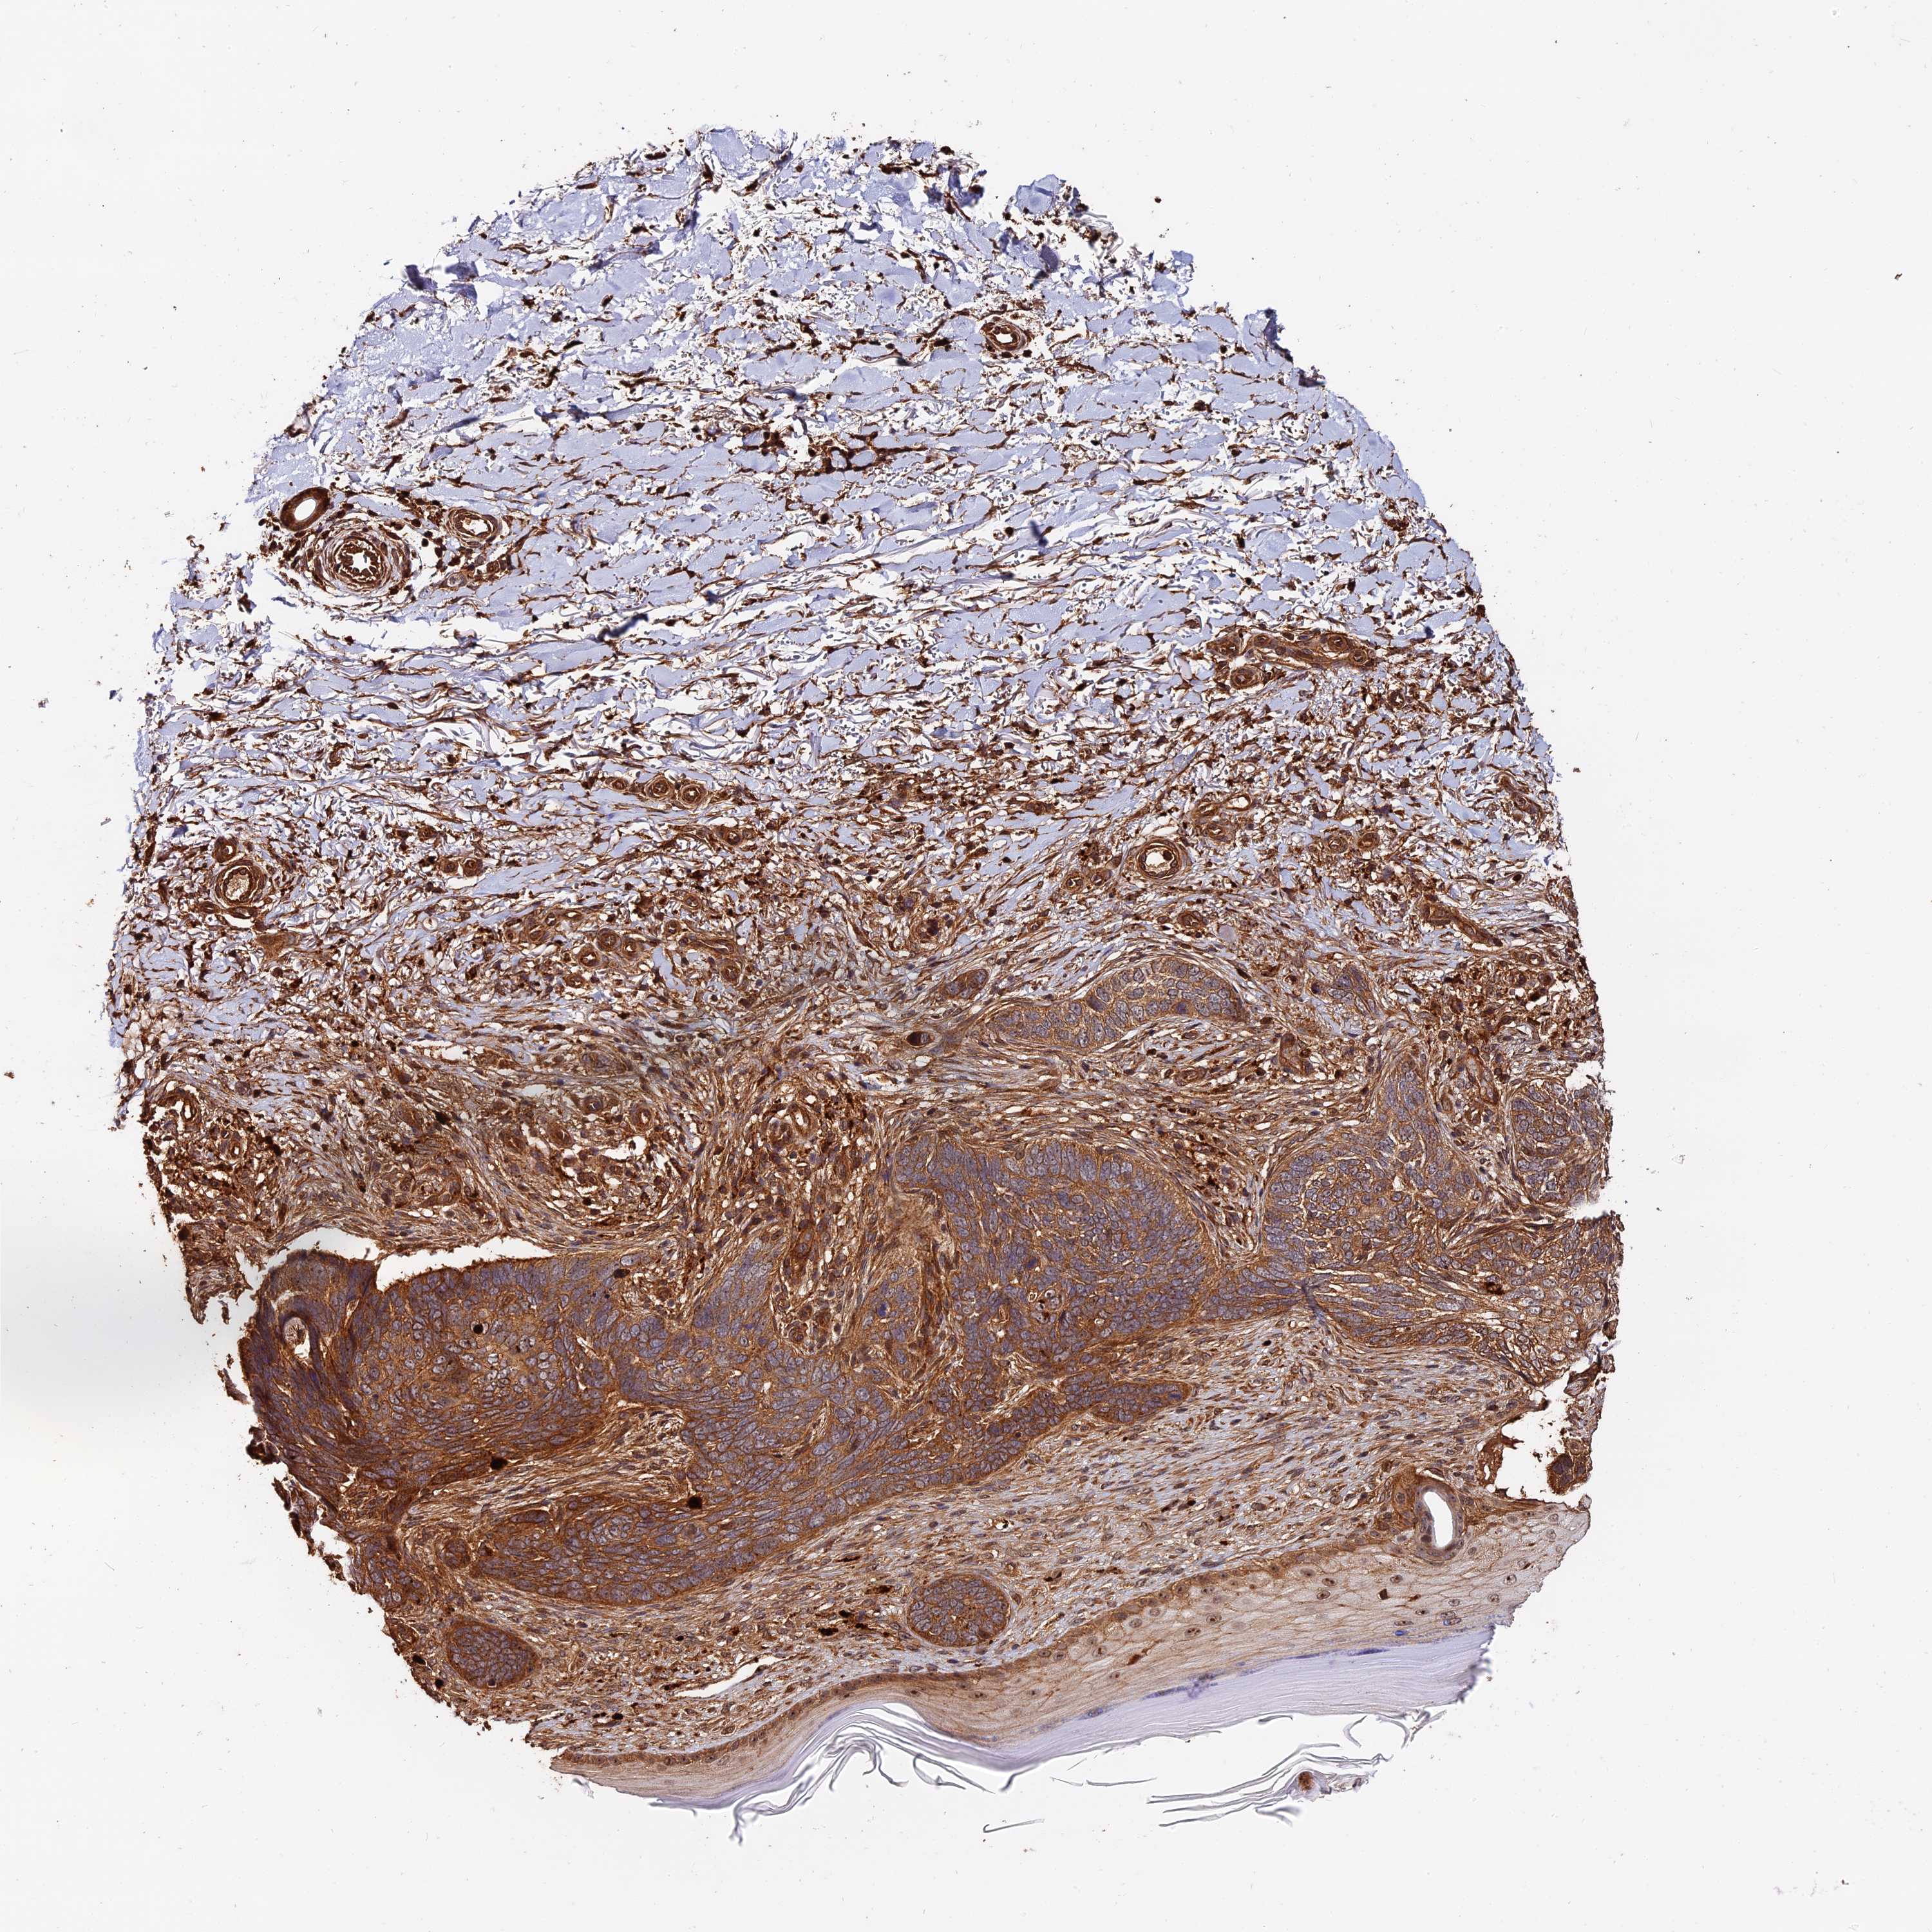

SKIN CANCER - Protein expressioni

A mouse-over function shows sample information and annotation data. Click on an image to view it in a full screen mode. Samples can be filtered based on level of antibody staining by selecting one or several of the following categories: high, medium, low and not detected. The assay and annotation is described here.

Antibody staining in the annotated cell types in the current human tissue is reported as not detected, low, medium, or high, based on conventional immunohistochemistry profiling in selected tissues. This score is based on the combination of the staining intensity and fraction of stained cells.

Each image is clickable and will lead to virtual microscopy that enables deeper exploration of all samples and also displays staining intensity scores, fraction scores and subcellular localization as well as patient and tissue information for each sample.

Basal cell carcinoma

Squamous cell carcinoma, NOS

Squamous cell carcinoma, metastatic, NOS